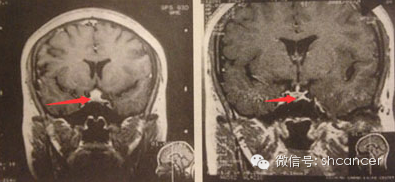

案例三:患者女,40岁,垂体腺瘤。进行伽玛刀治疗5个月后进行复查肿瘤明显缩小了,治疗后15个月复查没复发。目前临床症状改善。